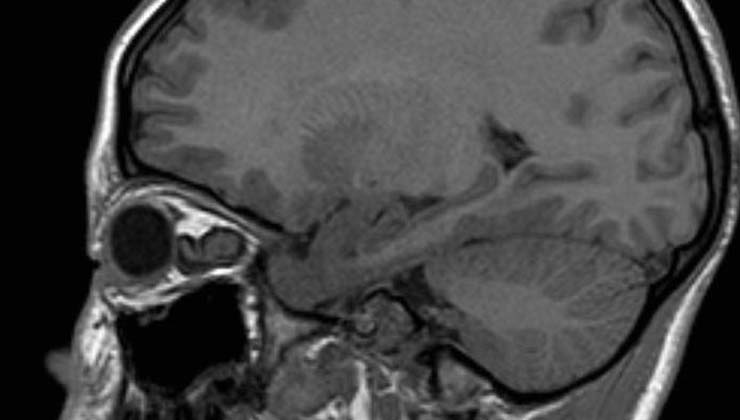

¿Cómo se diagnostican?

Para diagnosticar los tumores con afectación neuroftalmológica es necesaria una completa exploración oftalmológica, que suele incluir:

En paralelo, son necesarias pruebas complementarias, como una resonancia magnética o la tomografía computerizada.